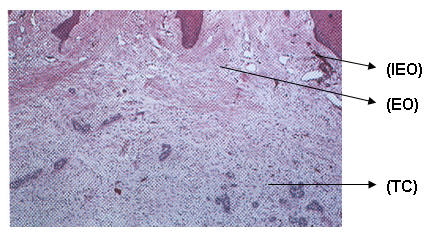

Desde el punto de vista histopatológica la lesión es básicamente fibrosa, contiene múltiples islotes pequeños y hebras de epitelio odontógeno que se asemejan a residuos de la lámina dental. El tejido conjuntivo inmediatamente adyacentes a los islotes epiteliales son menos denso y mixomatozo.